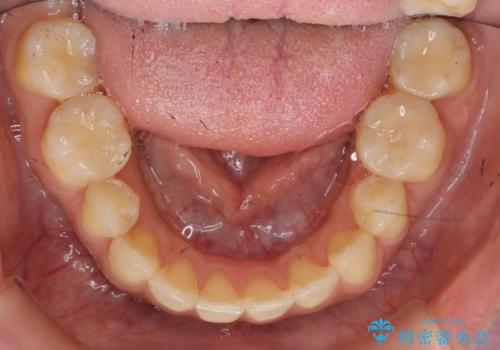

神経の死んだ歯の変色 前歯審美回復セラミック治療

- 以前治療した前歯の変色の改善を希望され来院されました。

X線写真より根管治療(歯の神経の治療)が以前になされており、歯の神経がないまま経過したことによる変色とわかりました。

根尖周囲に病変や自覚症状もありませんでしたが、以前に治療したのが約20年前とのことで

再根管治療→ファイバーコア築盛→セラミッククラウン作製

の流れで審美性回復の計画を立てます。